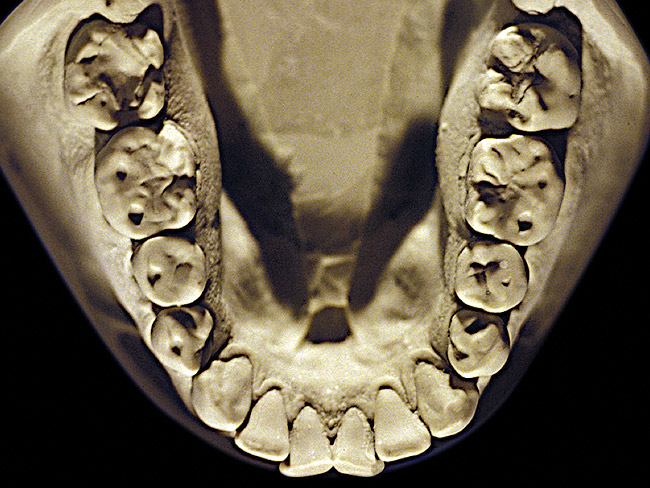

Figure 2  Advanced NCLTS from bruxism, mandibular arch.

Figure 2

The patient shown in Figure 3 and Figure 4 exhibited severe NCLTS from bruxism. Examination of the casts indicated that the NCLTS was progressively greater toward the anterior teeth. Cupping and cratering was not present because there was no secondary cause. Figure 5 and Figure 6 detail another bruxism patient, but to a lesser degree and one with cupping/cratering caused by toothpaste. The cups or craters were not caused from bruxism because the teeth could not touch the bottom of the invaginations. In both featured patients, upon hand-articulating the casts, the NCLTS facets matched up and the diagnosis of bruxism was confirmed.